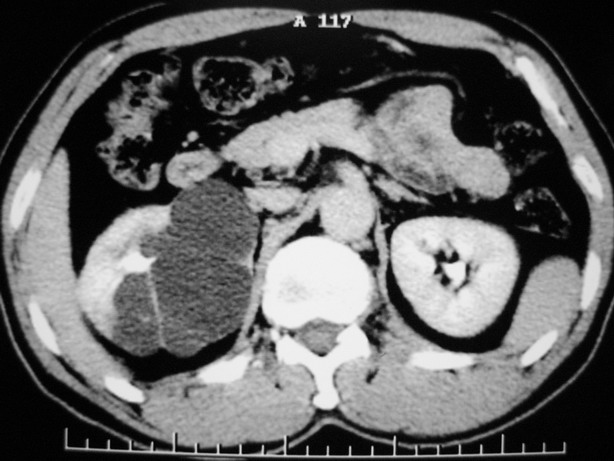

男性,48,体检发现,平时无症状。

肾盂旁多囊性占位,有实性成分,增强有轻度强化,收集期病变内无造影剂显影。诊断肾盂旁囊肿,有实性成分无法解释,查书后诊断为:多房性囊性肾瘤!!不知大家同意否?????????对本病知道不多,望大家不吝赐教!!

不除外囊性肾癌

支持囊性肾癌。

右肾多发囊性低密度影,囊内有增强的隔及实性组织,考虑囊性肾癌。